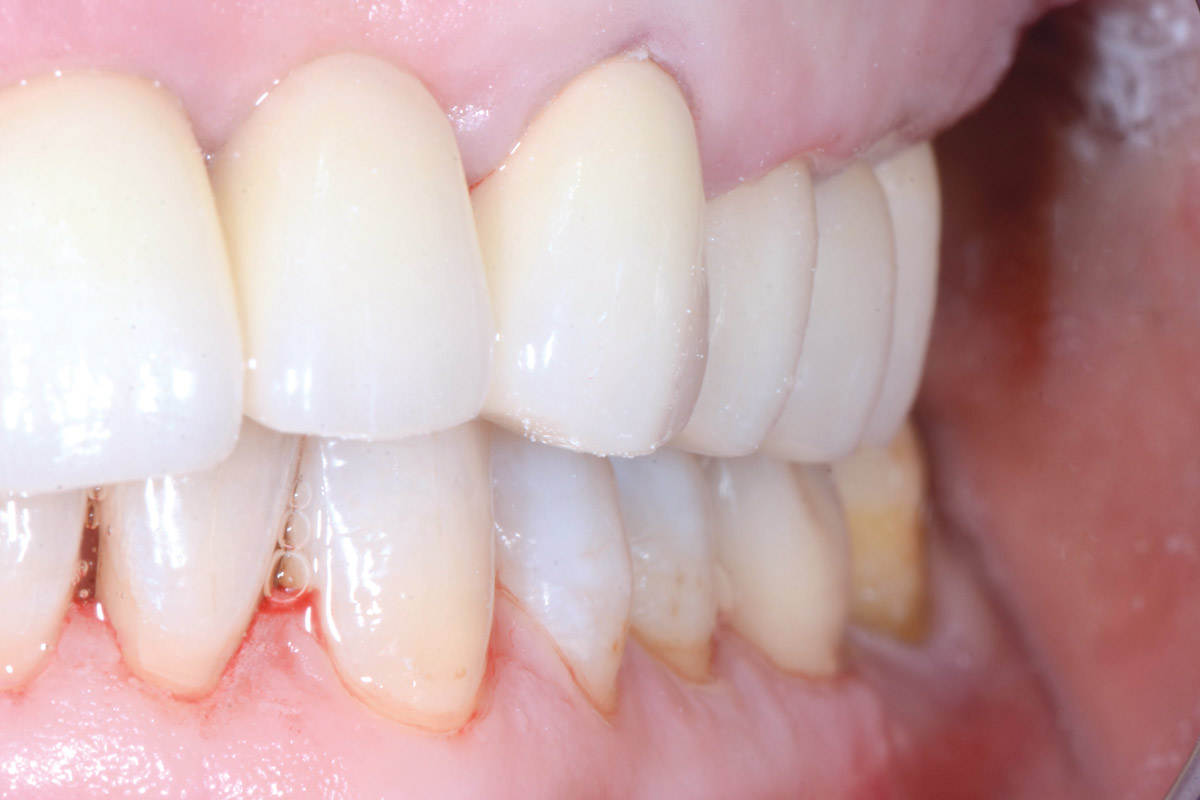

Initial view of the case. Discoloration of 1.1 and mild class I gingival recession